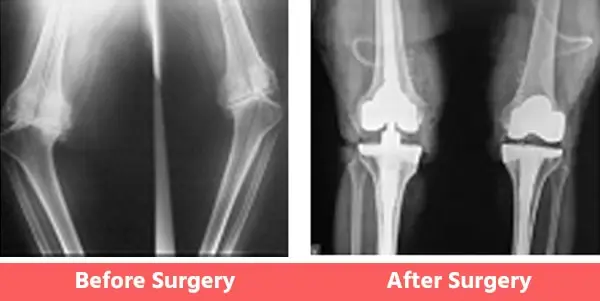

People may have certain deformities of the knee which include bow legs (varus), knock knees (valgus), or even wind-swept legs.

In such cases, the surgeon has to be well-experienced in handling such cases and should also have had considerable experience with revision joint replacement surgeries as well. See below Images.

1. Bow Legs (Varus Knee)

Some Common Deformities

1. Bow legs (Varus)

You can see illustration and X-Ray images shown above already.